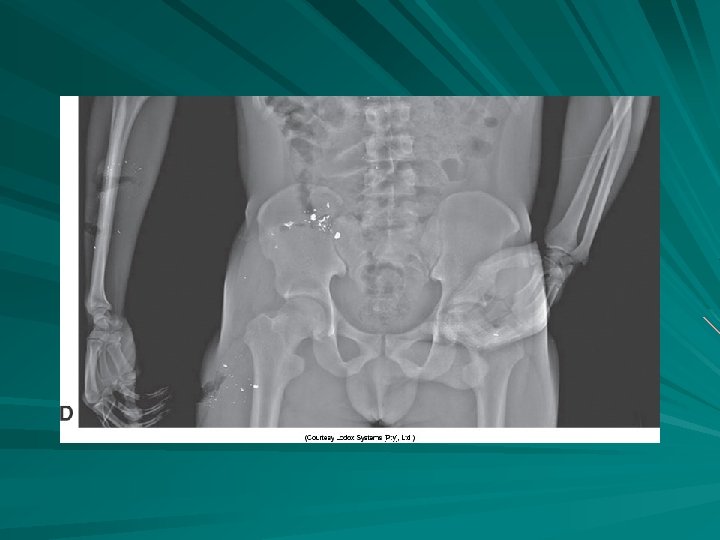

Zoomed lower pelvis demonstrating multiple fractures (arrows).